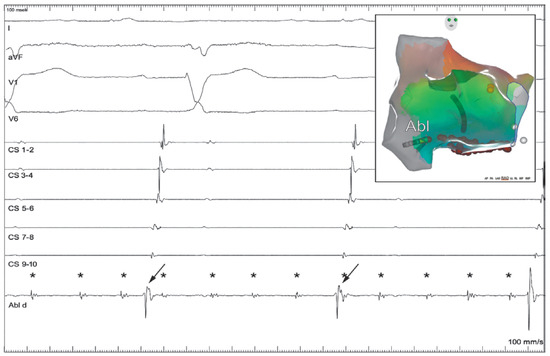

The Eustachian ridge is ablated as part of the cavotricuspid isthmus (CTI) involved in typical atrial flutter (AFL) ablation, but is itself rarely an arrhythmogenic focus. We report a case of a patient with dual tachycardia involving the CTI area....